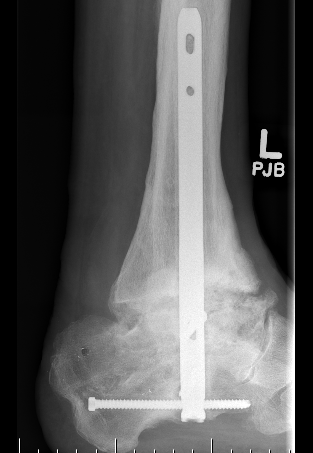

B. Lateral approach and fibular osteotomy

Zimmer Biomet Trabecular Metal PDF

Vumedi fibula osteotomy approach for total ankle arthroplasty